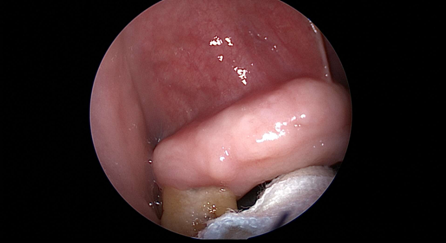

近日(ri),耳鼻喉科(ke)成(cheng)功開展(zhan)1例鼻內(nei)鏡下含牙囊腫切除術(shù)。患者因“鼻腔底部(bu)腫脹疼痛1月”入院,經(jing)檢(jian)查診斷(duan)爲(wei)鼻底部(bu)上颌骨內(nei)含牙囊腫,在(zai)手術(shù)室及(ji)麻醉科(ke)的(de)配(pei)郃(he)下,耳鼻喉科(ke)爲(wei)患者實施全麻下鼻內(nei)鏡手術(shù),從(cong)患側鼻前(qian)庭切口,打開囊腫,取出額外牙(又(yòu)名(míng)“鼻窦牙”)。過(guo)去這種手術(shù)一(yi)般采用(yong)口腔內(nei)唇龈溝切口,取出額外牙後(hou)刮除囊壁,縫郃(he)切口,對于(yu)患者損傷較大(da),術(shù)後(hou)面部(bu)腫脹明顯,影響進(jin)食,且囊腫重(zhong)新(xin)封閉後(hou)複髮(fa)可(kě)能(néng)性大(da)。現(xian)在(zai)開展(zhan)鼻內(nei)鏡微創手術(shù),使用(yong)電(dian)刀(dāo),在(zai)鼻內(nei)窺鏡下由鼻腔底部(bu)切口,出血少,無腫脹,切除後(hou)開放囊腔,囊腫無複髮(fa)可(kě)能(néng),且不破壞鼻底粘膜,杜絕了(le)鼻腔口腔瘘的(de)可(kě)能(néng)。(耳鼻喉科(ke))